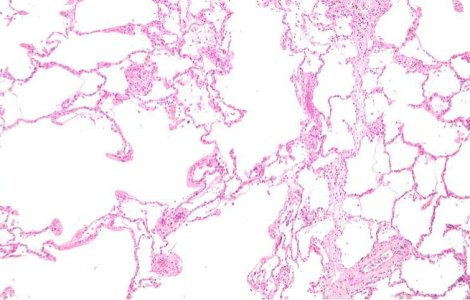

Tehnica inovatoare: Au fost descoperite celulele susa care ajuta la regenerarea plamanilor.